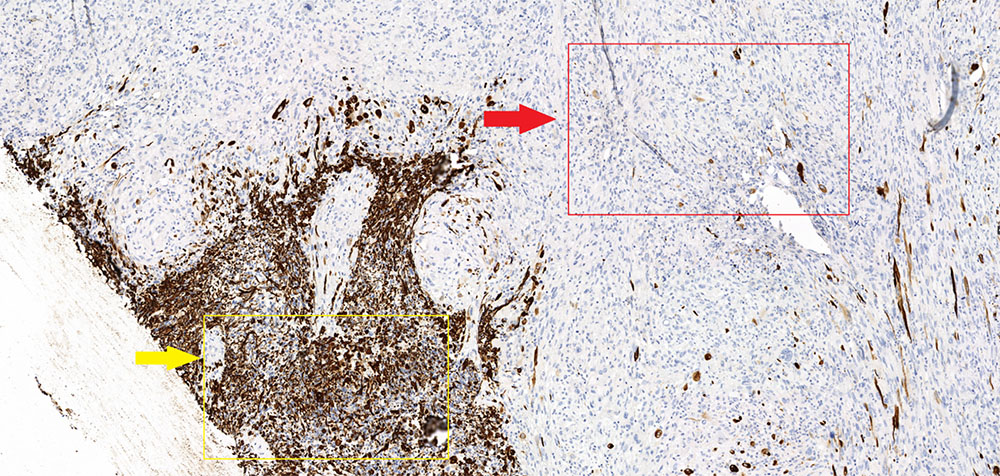

Глиосаркома  (послеоперационный препарат), окраска гематоксилином и эозином, увеличение х10. Глиальная часть демонстрирует выраженный ядерный полиморфизм и клеточную атипию. Саркоматозная часть представлена веретеновидной формы клетками с ретикулиновыми волокнами (соединительная (мезенхимальная) ткань).

Маркер GFAP (специфичный глиальный фибриллярный кислый белок) – демонстрирует характерную выраженную экспессию в глиальной части опухоли (желтая стрелка) и полное отсутствие экспрессии в саркоматозной (красная стрелка). Кроме того в данном микропрепарате стоит отметить отчетливое преобладание саркоматозной части над глиальной.